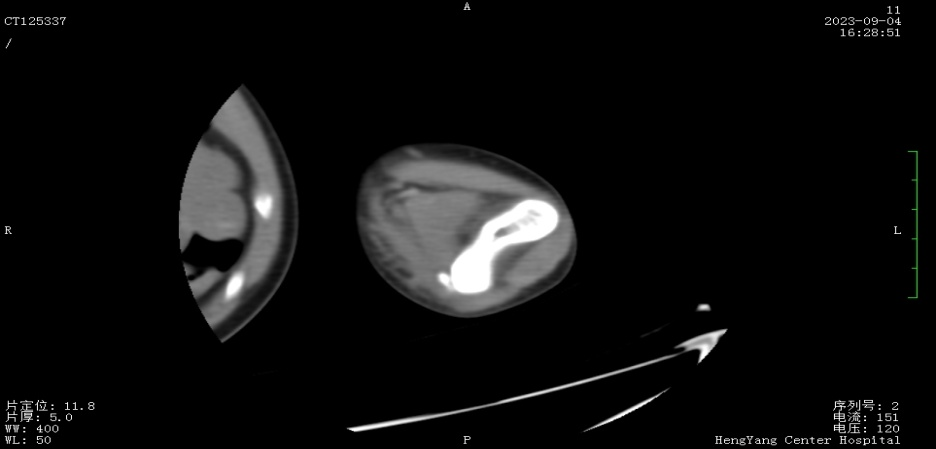

接診后,醫(yī)師發(fā)現(xiàn)小莫同學(xué)的左肘關(guān)節(jié)自然狀態(tài)下僅能伸展至約115°,并伴有習(xí)慣性屈肘。經(jīng)與骨科醫(yī)生溝通并閱片后,考慮骨化肌炎,針對(duì)這種情況,一般采取手法松解關(guān)節(jié)和關(guān)節(jié)功能鍛煉相結(jié)合的治療方案。但此方案常用于成人患者的關(guān)節(jié)粘連傳統(tǒng)松解術(shù)和關(guān)節(jié)松動(dòng)訓(xùn)練,對(duì)于兒童來說刺激強(qiáng)度太大,且因兒童骨骼及關(guān)節(jié)較成人脆弱,無法保證治療的連續(xù)性及安全性,若一味采取輕柔手法,不僅治療時(shí)間長(zhǎng)、見效慢,還可能加重后續(xù)治療難度